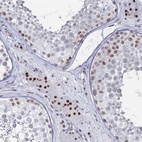

Immunohistochemical staining of human testis shows strong nuclear positivity in Leydig cells.